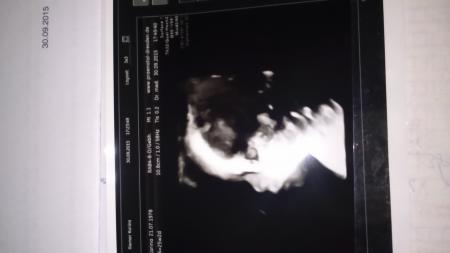

Was soll ich sagen, so schöne Bilder habe ich (wir) noch nicht gesehen und ich war hin und weg!

Mit dem kleinen Mann ist alles bestens, 855 g wiegt er jetzt ca.alles dran was dran sein muss und muss zugeben ich war skeptisch was die Kontrolle angeht aber jetzt bin ich beruhigt! In der 30 ssw soll noch mal kontrolliert werden ob der kleine gut versorgt wird (hatte ja beim ersten kind eine plazentainsufizienz)!

Ich versuche es mal ob es klappt mit dem Bild...